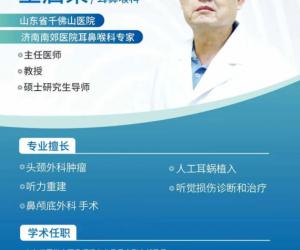

- 11-23秋冬耳鼻喉疾病高发!千佛山医院王启荣主任定期坐诊济南南郊医院

- 11-23秋冬耳鼻喉疾病高发!千佛